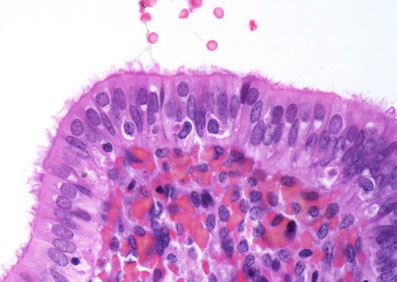

Herpes Simplex Virus (HSV) Cervicitis

In early phases see homogenous cells in basal layer c nuclear or cytoplasmic vacuolization, which then moves up into intermediate cell layer and forms bullae that rupture and ulcerate causing epithelial cell necrosis and inc inflam

- ground glass chromatin in nuclei

Follicular cervicitis

Assoc c chlamydia infx

- see tingible body macrophages in lymph nodes

Follicular cervicitis c macrophage inclusion, assoc c chlamydia infx